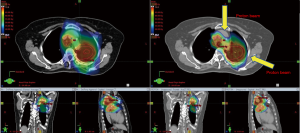

The promise of proton therapy lies heavily on the existence of a Bragg peak, a narrow region where the dose deposition peaks and falls off sharply as shown in Figure 2. Protons with higher energies deposit their maximum dose at greater depths. By accumulating weighted dose depositions over a range of proton energies, a spread-out Bragg peak (SOBP) can be obtained. This is shown in Figure 3, where the proportion of proton fluence with energies 139, 137, 131, and 125 MeV are 0.32, 0.28, 0.23 and 0.17 respectively. Using more energies between the range 125 to 137 MeV, a more uniform “flat top” depth dose can be attained. By designing proper beam entries, a very conformal dose distribution can be achieved using proton therapy, with sufficiently coverage of the clinical tumour volume (CTV), and minimal dose to the OARs which are beyond the range of the maximum energy protons (16,17). An example is as shown in Figure 4.